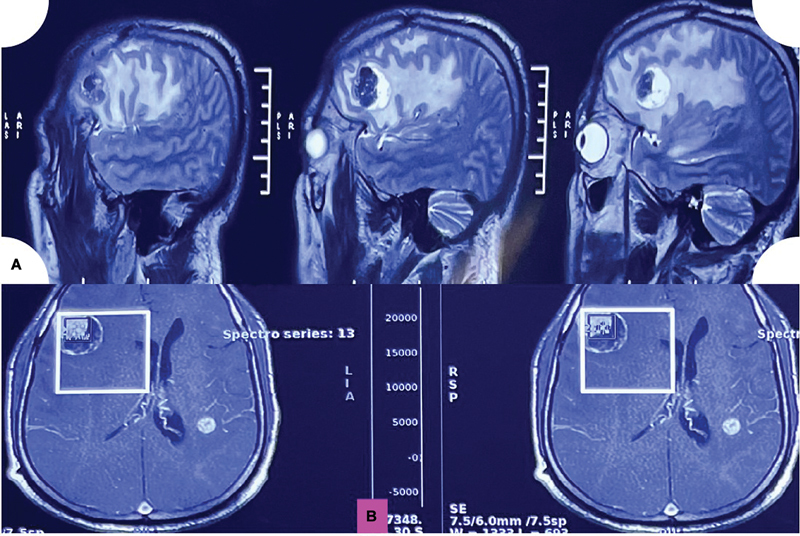

Primary intracranial melanomas are an extremely rare entity and are a diagnosis of exclusion. Malignant melanoma represents the third most common site for cerebral metastasis. We hereby narrate a comprehensive and detailed case of metastatic intracranial melanomas with BRAF mutation, which later on had an extensive systemic spread. The imaging differentials include metastasis, intracranial hemorrhage, or granuloma. The final and definitive diagnosis was attained by detailed clinical, histological, and immunohistochemical evaluation as metastatic malignant pigmented tumor consistent with intracranial melanoma.